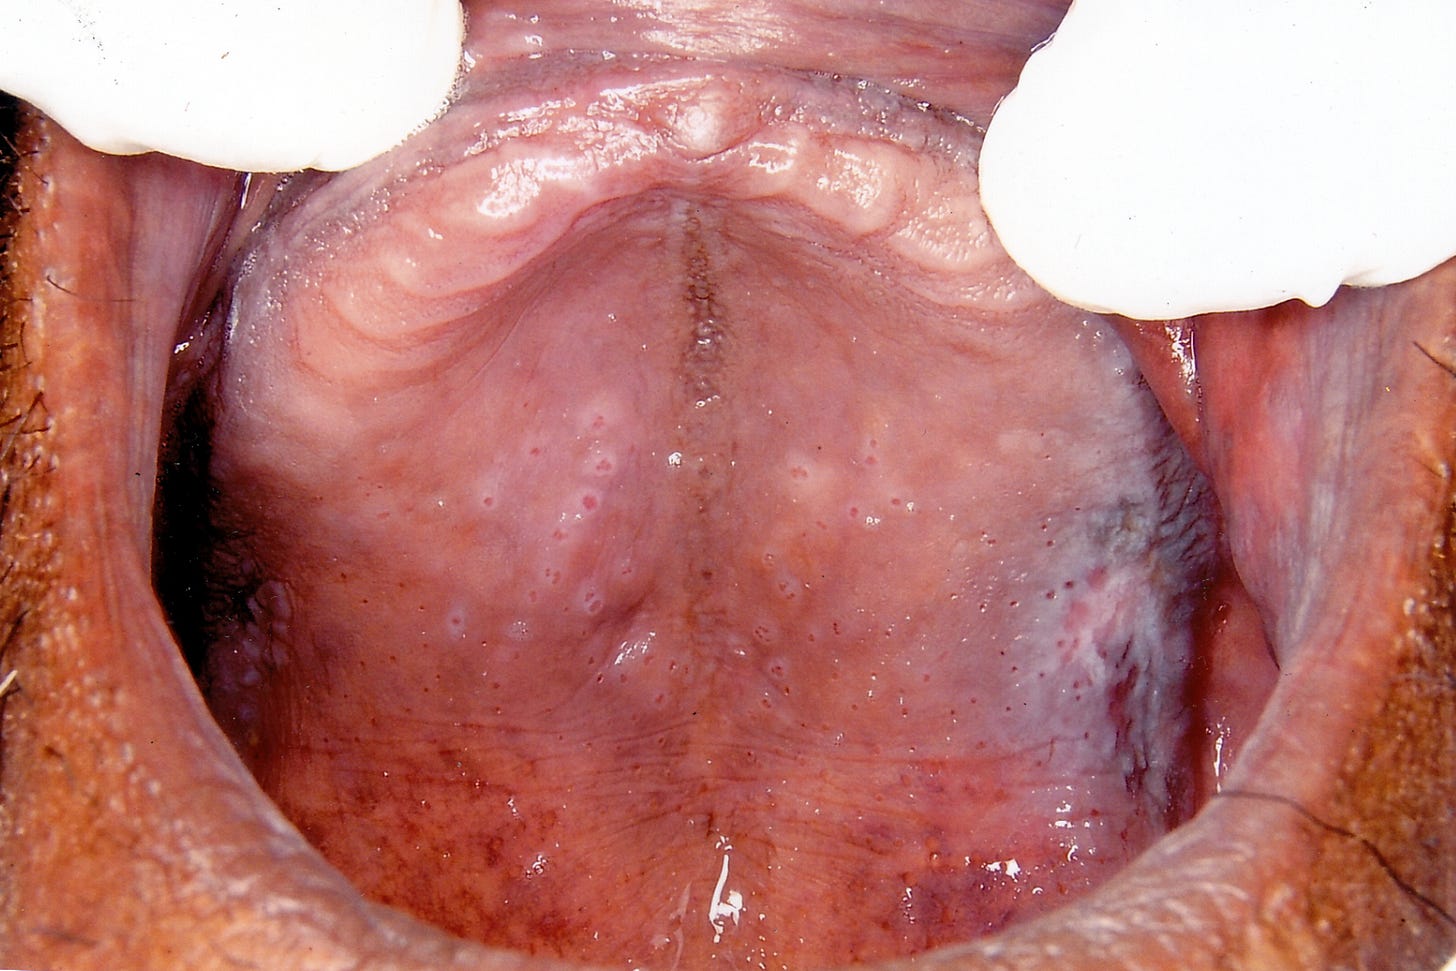

NS is a diffuse white, keratotic lesion with numerous raised papules that have red punctate centres.

The lesion is usually fissured or wrinkled.

The raised papules with red centres represent inflamed minor salivary gland ducts.

The lesion starts of as diffuse erythema and progresses to become white, thickened, fissured and wrinkled.